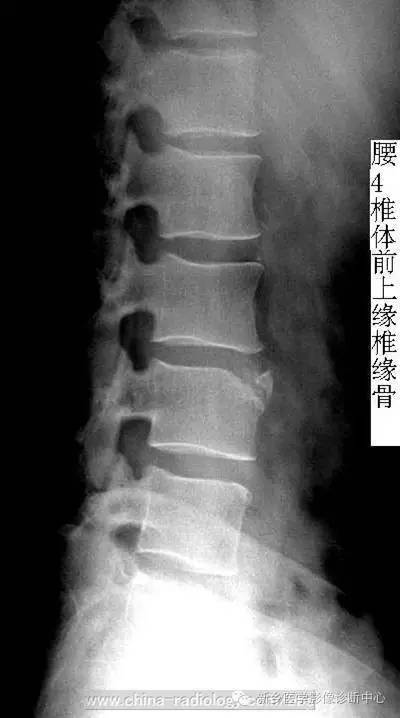

• 椎缘骨/软骨结节,一个偶尔会遇到的疾病

椎缘骨/软骨结节,一个偶尔会遇到的疾病